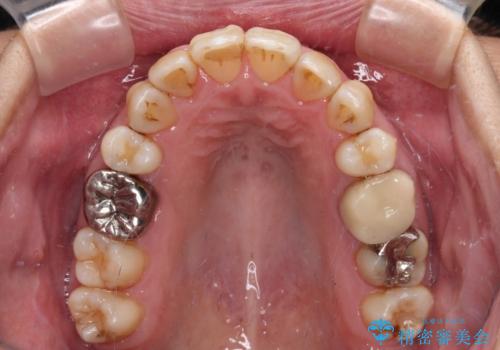

- かつて抜歯矯正を行ったものの、後戻りをしてしまったとのことで来院された患者様です。

上顎前歯が前突し、隣の歯が裏側に移動してきている状態でした。

日頃から飲まれる飲み物の影響で着色しやすいため、来院の度に着色除去のクリーニングも行っていました。